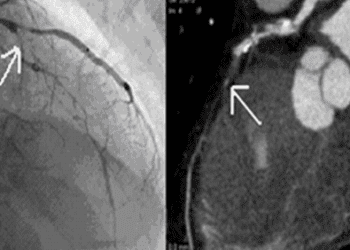

The rates of hospital admission for STEMI per 100,000 individuals increased from 3.7 in 2001, 8.1 in 2006, to 15.8 in 2011 (p<0.0001). There was an increase in aspirin use within 24 hours from 79.3% (95% Confidence Interval [CI] 77.3-81.3) in 2001 to 91.2% (95% CI 90.5-91.9) in 2011 (p<0.0001), as well as clopidogrel use from 1.5% (95% CI 0.9-2.1) in 2001 to 80.7% (95% CI 79.8–81.6) in 2011 (p<0.0001). Use of primary percutaneous coronary intervention increased between 2001 and 2011 from 10.2% (95% CI 8.1-12.3) to 27.6% (95% CI 26.1-29.1; p<0.0001), while fibrinolytic therapy decreased from 45.0% (95% CI 41.5-48.5) to 27.4% (95% CI 25.9-28.9; p<0.0001). The proportion of patients that did not receive reperfusion did not significantly change (44.8% [95% CI 41.3-48.3] in 2001 vs. 45.0% [43.3–46.7] in 2011, p=0·82). The median hospital stay length decreased from 13 days (interquartile range, IQR 7-18) in 2001, to 11 days (IQR 6-16) in 2006, and 11 days (IQR 7-14) in 2011 (p<0.0001). The adjusted in-hospital mortality did not significantly change between 2001 and 2011 (Odds Ratio 0.84, 95% CI 0.62–1.12, p=0.06).